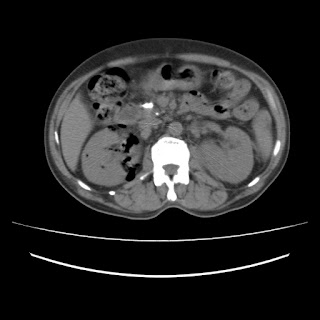

THIS IS A CASE OF EMPHYSEMATOUS PYELONEPHRITIS ON RIGHT SIDE AND PYELONEPHRITIS ON THE LEFT SIDE WITH ENCEPHALOPATHY SECONDARY TO SEPSIS IN A DIABETIC PATIENT

CT

Right Emphysematous Pyelonephritis with Left Acute Pyelonephritis with Encephalopathy secondary to Sepsis